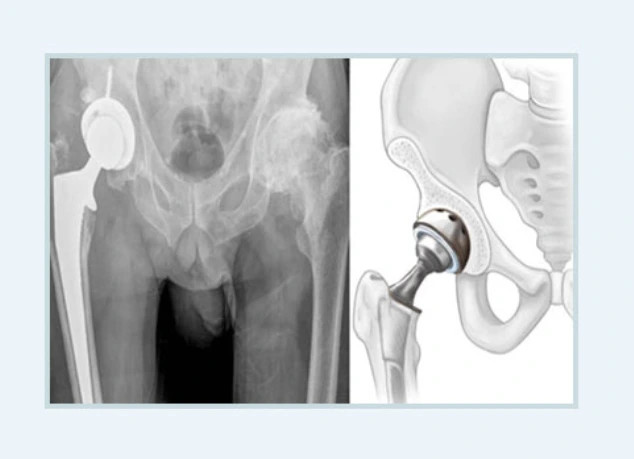

인공관절치환술

아주 심각하게 대퇴골두의 변형 및 함몰이 발견되었을 때 고려하는 수술적 치료로 증상에 따라 자기 관절을 살리지 못한다면 불가피한 수술이지요.

이미 손상된 비구와 대퇴골두를 특수 제작된 인공관절로 대체하는 치료법으로 대퇴골두무혈성괴사로 인한 통증이 심하거나 관절 운동에 장애가 생긴다면 고려해야 합니다.

인공관절치환술.PNG